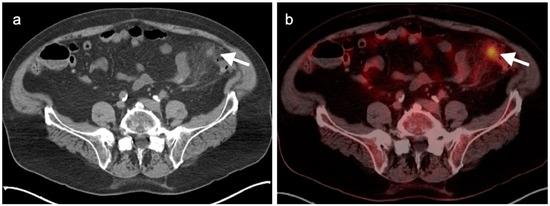

9. Bowel Adenocarcinoma: Colon, Rectum, Small Bowel

10. Anal Carcinoma